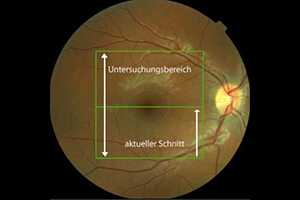

Fundusfotographie

Mit einer Funduskamera, einer speziell für die Netzhautfotografie entwickelte Kamera, werden Veränderungen an der Netzhaut zur Sicherheit fotografisch untersucht und dokumentiert. Wegen der hohen Auflösung und je nach Aufnahmewinkel ermöglicht sie präzise Aufnahmen insbesondere des Sehnerven, der Netzhaut, der Blutgefäße und der Aderhaut. Spezielle Filter liefern dabei Informationen, die bei der einfachen augenärztlichen Untersuchung verborgen bleiben. Der Vergleich von Aufnahmen, die zu unterschiedlichen Zeitpunkten aufgenommen wurden, ermöglicht eine genaue Beobachtung von Krankheitsverläufen. Bei Veränderungen kann somit zeitnah eine entsprechende Therapie oder Therapieanpassung vorgenommen werden.

Was passiert bei der fotografischen Untersuchung?

Bei weitgestellter Pupille (Achtung: keine Fahrtauglichkeit für mindestens 4 Stunden nach der Untersuchung!) werden mit Hilfe eines Auslösers nacheinander mehrere Bilder von der Netzhaut angefertigt. Die Untersuchung ist berührungsfrei und dauert nur wenige Minuten.

Was kann ich von der fotografischen Dokumentation erwarten?

Durch die Farbfotografien können wir sehr viel genauer das aktuelle Stadium der Erkrankung mit den Ergebnissen der vorangegangenen und künftiger Untersuchungen vergleichen. Selbst kleine Veränderungen lassen sich zuverlässig beurteilen. Am Computerbildschirm können wir Ihnen die Befunde im Anschluss an die Untersuchung nachvollziehbar erläutern und – wenn es erforderlich ist – gemeinsam mit Ihnen das weitere therapeutische Vorgehen besprechen.

In den meisten Fällen ist die Untersuchung mittels einer speziellen Ultra-Weitwinkel Kamera eine komfortable Alternative. Die berührungslose Aufnahme ermöglicht eine nahezu vollständige Untersuchung der Retina - die Gabe von Augentropfen ist nicht notwendig, so dass Sie im Anschluss keinerlei Einschränkungen haben.

Optos Ultra-Weitwinkel Netzhautuntersuchung